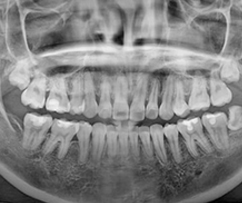

3D CT 촬영으로 치아와 치조골의 상태 및

잇몸뼈의 양과 길이 등의 상태를 정확하게

측정하여 세밀한 진단과 시술 전 발생가능한

문제점을 사전에 발견하고 대비하여

진료의 안정성을 높힙니다.

치과진료는 굉장히 세밀한 치료이기 때문에 정밀한 3D 디지털 기술을 접목하면

의료진의 판단에만 의존하던 치료를 더욱 정확하게 예측하고 진하여 오차를 줄일 수 있습니다.